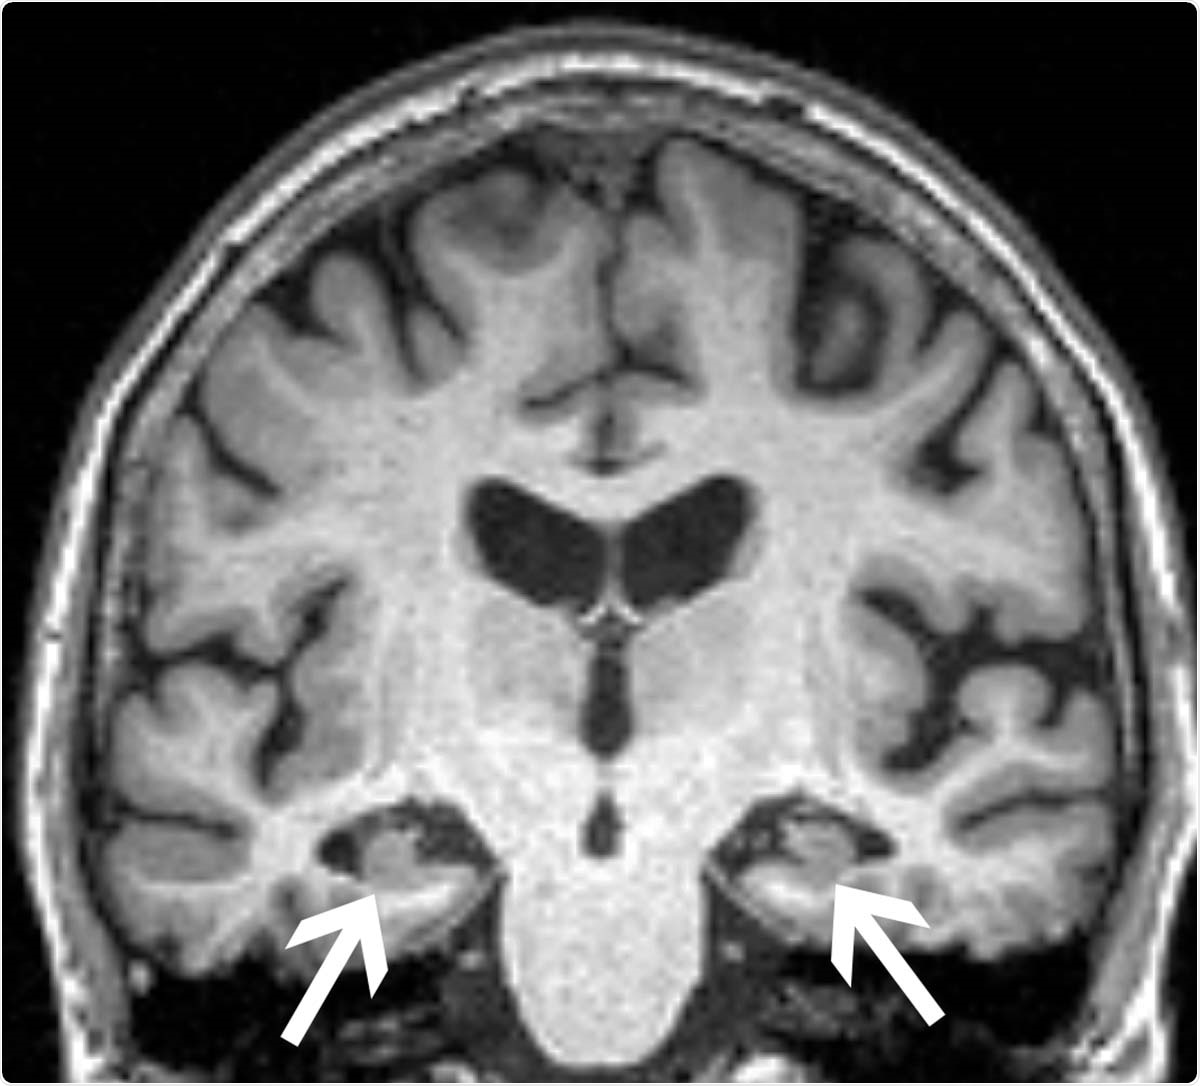

MRIs of the patients’ brains were analyzed to establish the baseline volumes of two key areas implicated in memory formation, the hippocampus, and the entorhinal cortex. The researchers also determined whether patients had the ApoE4 allele, known to be the most prevalent genetic risk factor for Alzheimer's disease. Additionally, the researchers used clinical surveys to measure anxiety.

The results showed that patients who went on to obtain a diagnosis of Alzheimer's disease were those who had significantly lower hippocampal volumes at the onset of the study. They also had reduced volumes of the entorhinal cortex and were more likely to have the ApoE4 allele. These findings were expected.